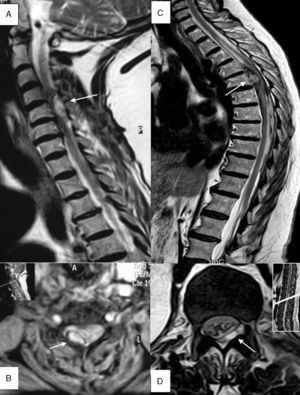

Pruebas diagnósticasLa mediana de tiempo que transcurrió desde el inicio de los síntomas hasta la consulta en urgencias fue de 6,5 h (RIC 1-48). La mediana de tiempo que transcurrió desde el inicio de los síntomas hasta disponer de una valoración por un neurólogo de guardia fue de 14 h (RIC 5-72). Se realizó una RM espinal a todos los pacientes. La mediana de tiempo que transcurrió desde el inicio de la clínica hasta su realización fue de 28 h (RIC 10-101). Se realizó una prueba de imagen previa a la RM espinal en 7 pacientes: radiografía simple de columna a 3, tomografía computarizada (TC) de cráneo a 2 y TC de columna a 3. De los 3 pacientes a los que se les hizo TC de columna, en 2 se evidenció una colección extramedular hiperdensa indicativa de hematoma epidural espinal. A 2 pacientes se les hizo angiografía tras haber sido diagnosticados mediante RM sin encontrar alteraciones patológicas. La mediana de tiempo desde la llegada a urgencias hasta la realización de la RM fue similar en los pacientes a quienes se les realizó solo RM (20 h, RIC 7-74) y en quienes recibieron otras pruebas diagnósticas previamente (20 h, RIC 4-48). Los principales hallazgos radiológicos se encuentran resumidos en la tabla 2. En la Figura 1 se muestran algunos ejemplos de RM espinal.

A) Paciente 4, corte sagital, secuencia T2 TSE. Hematoma epidural (flecha) en región posterior derecha localizado entre segmentos C4-C6 que ejerce importante efecto compresivo sobre la médula produciendo mielopatía. B) Paciente 4, EG T2* (estrella), corte axial a nivel C4 donde se identifica el hematoma en región posterior derecha (flecha). C) Paciente 1, corte sagital, secuencia T2 TSE. Hematoma epidural (flecha) de predominio anterior entre segmentos D6-L2 con compresión medular y signos de mielopatía asociada. D) Paciente 11, T2 TSE, corte axial a nivel D12-L1, hematoma epidural (flecha) en región lateral y posterior, con desplazamiento y compresión del saco tecal.